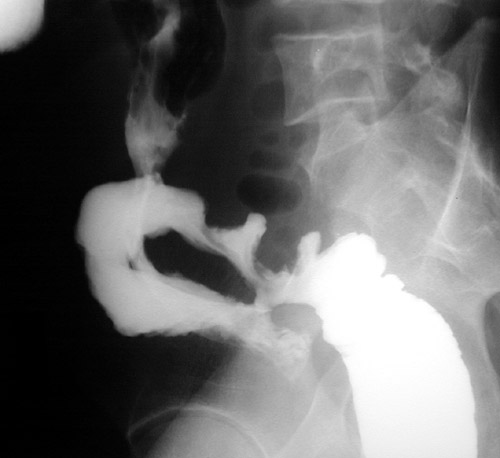

The barium enema seen here demonstrates fistulae in a case of Crohn's disease. Loops of small bowel and colon converge in an area of adhesions resulting from the transmural inflammation.